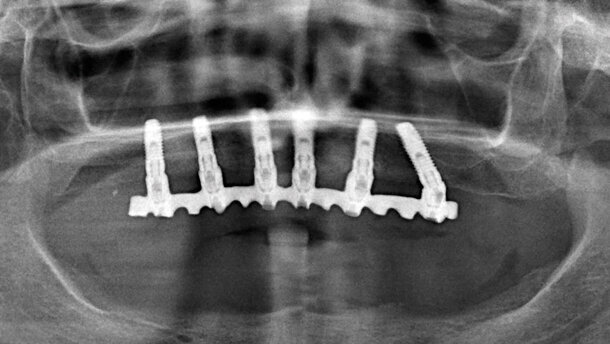

I pazienti selezionati per la presente ricerca sono stati giudicati idonei in quanto rispondenti ai criteri generali e specifici minimi per l’inclusione: assenza di controindicazioni sistemiche assolute e relative per l’implantologia, sufficiente biodisponibilità ossea, comprensione individualizzata delle procedure implantoprotesiche cui sottoporsi supportata dalla sottoscrizione del consenso informato, acquisizione delle norme di igiene orale e domiciliare postoperatorie, accettazione ed esecuzione dei protocolli farmacologici pre e postoperatori (Figg. 1, 2).

Esauste le procedure di isolamento intraoperatorio a scopo di asepsi chirurgica, si è provveduto all’incorporazione degli inserti alloplastici, in ossequio ai protocolli operativi raccomandati dalla casa produttrice per i carichi immediati (Fig. 3).

Previa corticotomia con fresa di alesaggio start, destinata alla determinazione del centro-cresta chirurgico e protesico, si è proceduto alla perforazione di profondità utilizzando la fresa mm 2,3. Con la successiva fresa countersink pylot (mm 2,95) si è ottenuto l’ampliamento della corticotomia in diametro (mm 3) e profondità (mm 3). Questi passaggi sono stati eseguiti con strumenti rotanti ad alta velocità (max 500 giri/min). Nella fase successiva, il sondaggio con il maschiatore scanner (definito per comodità “lettore”) ha permesso di identificare la classe ossea di appartenenza della parete ossea del tunnel implantare precedentemente allestito. Una volta determinato il grado di consistenza endocavitaria, l’operatore ha completato la preparazione del sito implantare mediante l’utilizzo di strumenti preordinati (alesatori e/o maschiatori), che hanno consentito l’allettamento dell’impianto fino ad ottenere livelli elevati di stabilità primaria media, consoni alle necessità protesiche di funzionalizzazione immediata. Nella disponibilità dell’operatore anche la scelta delle forze torcenti di inserimento, per permettere la modulazione dello stress di compressione, potenzialmente nocivo se incompatibile con le capacità di assorbimento termico del substrato biologico. In tutte le incorporazioni i dati alfa-numerici e diagrammatici hanno dimostrato la corrispondenza tra i valori di stabilità previsti e quelli effettivamente ottenuti a inserzione ultimata (Figg. 4-9).

Ad osteointegrazione avvenuta, è stata eseguita una riabilitazione avvitata con tecnologia Cad/Cam con rivestimento in resina o in ceramica (Figg. 10-13).